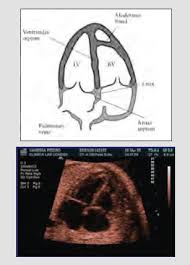

Nos referimos al diagnóstico fetal por ecocardiografía, que progresivamente se está implantando en las consultas ginecológicas. Hay cardiopatías que no son detectables como tal, pues incluso su existencia es normal y necesaria durante la vida fetal en el embarazo y sólo se constituyen en cardiopatías si persisten después de nacer el niño. Hay otras que existen, pero por su levedad no son detectables, manifestándose al nacer o incluso meses después del nacimiento. Hay otras progresivas que no se manifiestan en los estadios iniciales pero si finales. Hay finalmente otras que sí pueden detectarse a partir de la 16 semana de embarazo pero no siempre es fácil pues el niño está dando vueltas en el seno materno y no siempre tiene una adecuada posición para valorar el corazón, por lo que habría que ir a buscar la cardiopatía específicamente, lo que no es posible hacer de rutina en todas las embarazadas ya que el ginecólogo tendría que hacer lo mismo con los demás órganos.